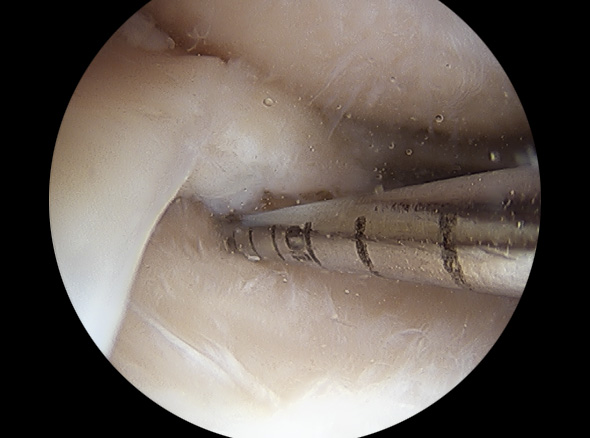

불안정한 반월상연골 부위를 내시경으로 확인하여 파열된 연골판을 꿰맴

약 7mm 정도의 2~3개의 작은 구멍을 무릎 관절 주변에 뚫고

초소형 카메라가 달린 내시경을 삽입한 후 내부를 확인하며

손상된 반월상 연골판을 다듬어줍니다.